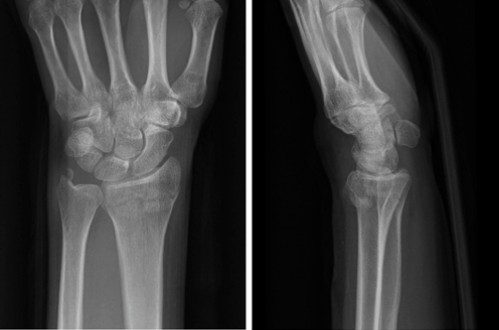

Primer ①